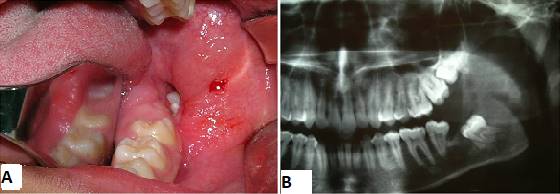

Male patient of African descent aged 17, a student born in Fortaleza, state of Ceará, Brazil, sought care in a private dental clinic with complaints of mouth suppuration. The patient’s mother informed us that he had felt a bad taste in his mouth for about a month. A clinical dental surgeon ordered a panoramic x-ray of the jaws, detected the lesion, and referred him to an oral and maxillofacial surgeon. His medical history did not include any complaints of pain: he had only reported a bad taste in the mouth and bad breath. The extraoral physical examination showed symmetrical facies and absence of facial deformities. Nodal chains of the cervicofacial complex presented no alterations. On intraoral examination, a suppuration was visible in the lingual and distal gingival sulcus in the region of tooth 37. There was a discrete elevation in the region of the left retromolar trigone with fluctuation point and liquid consistency. The panoramic radiograph showed an extensive osteolytic lesion in the left mandibular angle and ascending branch region, of expansive appearance, associated to and including tooth 38, displaced towards the basilar bone (Fig. 1).

A year after the first intervention, there was a clinically and radiographically significant reduction of the lesion (Figs. 6 A and 6 B). The next step was to enucleate the remaining cyst capsule and teeth 38, 18, 28, and 48 under general anesthesia.